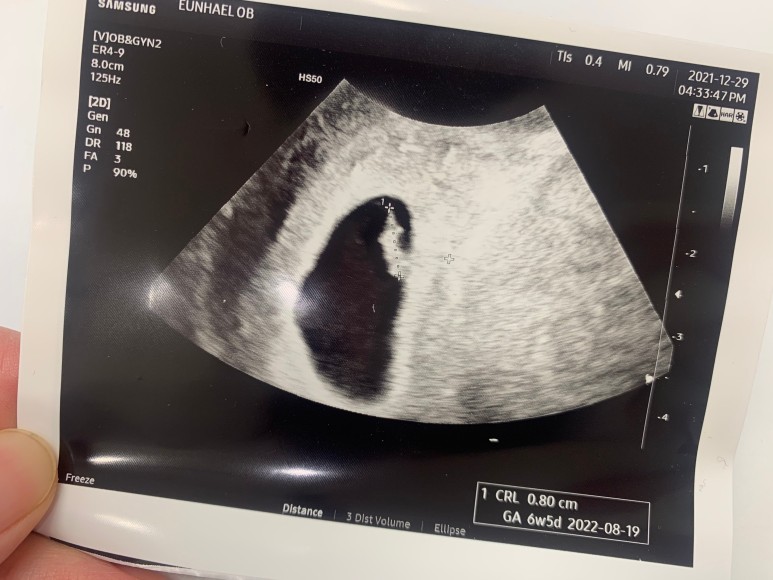

6주차에 임신인 걸 확인하고, 일주일 뒤인 7주차에 아기집 안에 아기가 빼꼼 자란 걸 확인했다.

무려 0.8cm! ㅋㅋ 도마뱀같았던 우리의 아가.

요랬던 도마뱀에서